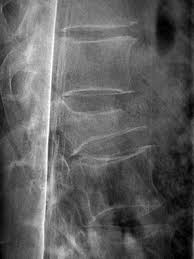

This radiograph is from an elderly woman who accidently fell down a flight of stairs.  She has had persistent back pain since that time.  Each student should add one piece of information to this case.  It can be to describe normal or abnormal things on the radiograph, a finding about whatever you think the diagnosis of this radiograph is, what is a symptom, or what you would do during physical examination.  Each blog post should be a different piece of information to lead us toward an accurate diagnosis.

Image result for Thoracic spine compression fracture

1. The first thing I notice is the obvious vertebral body height loss. The vertebral height loss, along with the traumatic incident and patient's age makes me believe this is a compression fracture.

10. In addition to the neuro screening that Dustyna mentioned, I would also try to rule out UMN involvement and cord compression by asking about B/B changes, check for Babinski, Hoffman's, Clonus testing, and ask about bilateral symptoms (quadrilateral symptoms not likely with level of injury).

ReplyDelete

28. This is an unstable compression fracture. The superior-anterior corner of the vertebral body is displaced from the rest of the vertebral body. There appears to be a linear zone of compression inferior to the superior vertebral endplate, which indicates an recent (<2 months old) compression fracture.